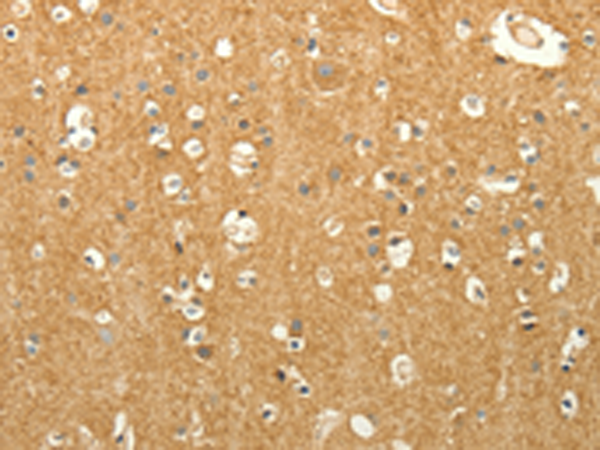

IHC positive control: |

Human brain and Human liver cancer |

IHC Recommend dilution: |

50-200 |